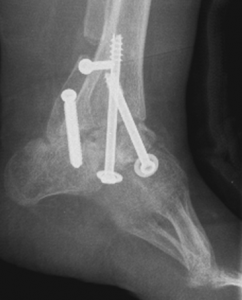

Dopo il terzo mese di vita, se necessario, si interviene chirurgicamente effettuando l’allungamento del tendine di Achille con tecnica percutanea.

Se l’intervento dovesse essere effettuato in età più avanzata, può rendersi necessario eseguire un intervento anche sulle ossa (osteotomie). Il rischio maggiore di questi interventi è quello delle recidive, queste deformità possono tendere cioè a ripresentarsi (in media nel 10% dei casi).